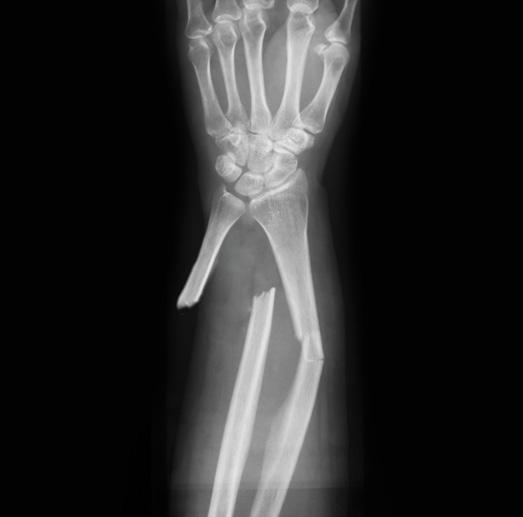

Ten to 15 times a month, medics in Galveston County follow an antibiotic protocol when treating open fractures.

The Galveston Area Ambulance Authority and Galveston County Emergency Services District No. 2 have had an active open fracture protocol for about two years.

“We found that often there was a missed opportunity for early antibiotics in patients with obvious or suspected open, long bone fractures,” said Dr. Kent Harkey, medical director for both EMS agencies. “We have a standing protocol where if an open fracture is suspected, we load IV Ancef (cefazolin) assuming there are not any contraindications—such as allergies to the medications.”

This protocol has received positive feedback from the Emergency Department at UTMB

“An open fracture requires different treatment than a closed fracture, in which there is no open wound. This is because, once the skin is broken, bacteria from dirt and other contaminants can enter the wound and cause infection. For this reason, early treatment for an open fracture focuses on preventing infection at the site of the injury.

The wound, tissues and bone must be cleaned during a surgical procedure as soon as possible. The fractured bone must also be stabilized to allow the wound to heal.”

and the surgeons, said Harkey, who is also a clinical assistant professor of medicine at UTMB as well as the assistant medical director of Emergency Medicine at the UTMB League City Campus.

“The American College of Surgeons were very supportive of this move in their last site visit to Galveston,” Harkey said.

Earlier administering of antibiotics for open fractures helps reduce the rate of infection, which often are serious and can lead to long-term complications. Bone infections are notoriously hard to permanently treat once they are established, often recurring over time and causing lifelong issues.

“I have standing orders in the form of protocols that empower the medics in the field to use their judgment and the best interest of the patient,” Harkey said.

The protocols go through indications, contraindications, dosing and pearls, which

are short and to-the-point tidbits of clinical information. When the medic suspects an open fracture, they use the protocol and administer the antibiotics. Some open fractures are obvious with the bone sticking out, but sometimes the bone retracts, and it appears to be just a laceration.

Harkey is collecting data to analyze the outcomes of this protocol.

“I have no doubt that the early antibiotics have helped with decreasing the morbidity and mortality associated with open fractures and severe trauma,” Harkey said. “It is my hope that as more agencies come under my medical direction, we can expand this protocol to help the citizens of Galveston County.”